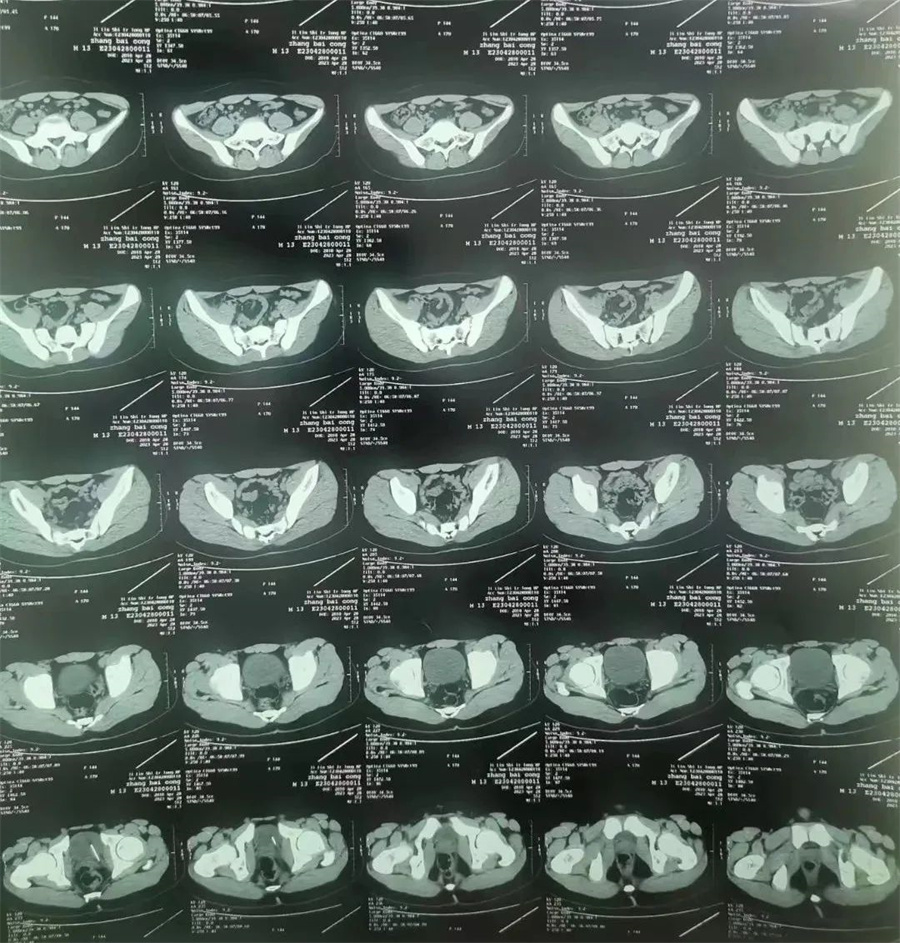

斌斌(化名),13岁,家住吉林市,因尿道疼痛、内裤有血,被家长带到当地医院就诊。医生经CT检查,发现斌斌膀胱侧壁扎着一根针,随时有穿破膀胱壁、损伤周围脏器可能。医生建议家长立即带斌斌到a片网站 进行手术,将针取出。

。泌尿外科主任谢方达为其开辟绿色通道,以最快的速度进行救治。谢方达主任利用膀胱镜探查,很快确认了针在膀胱内的具体位置。

由于针已经在膀胱内存留一年多,表面布满铁锈和陈渣,加之男孩尿道细长弯曲。如果强行经尿道取针,发生副损伤或尿道内异物存留的风险极大。

如何简捷、确切、迅速地将针取出成了最大难题。最终,谢方达主任决定利用腹腔镜在患儿膀胱上打孔,进行微创取针。当长度约4厘米、表面锈迹斑斑的针呈现在众人面前时,家长紧张焦虑的心情终于缓解了。

术后,谢方达主任说,经过长时间的腐蚀,针变得非常脆,一夹就碎,不断掉渣,好在经过灌洗,残渣被冲洗干净了。